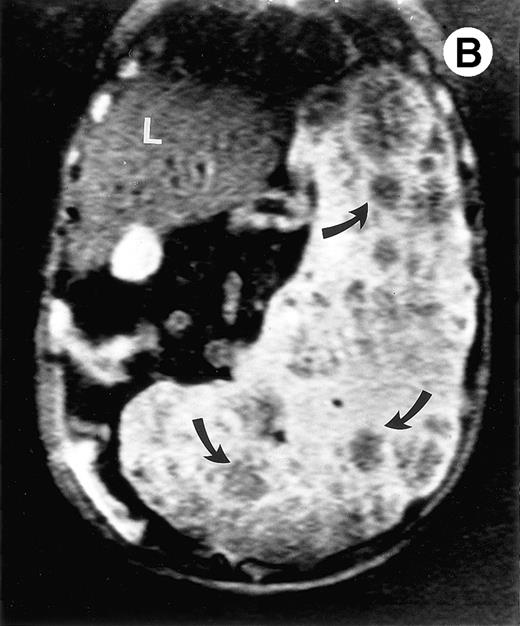

Surgical pathology showed a 6.5-kg spleen with nodular appearing external surfaces and focal subcapsular infarcts, ranging in size from 0.5 to 3.4 cm. Serial sections showed rubbery and focally fibrotic surfaces (Fig 2A). This correlated with his presurgical axial T2-weighted MRI, which demonstrated multiple low signal intensity nodules not seen on T1-weighted views (Fig 2B through D). Although MRI is useful in monitoring response to therapy, this case demonstrates that volumetric measurements alone may not be adequate, especially when there are multiple areas of decreased signal intensity on T2-weighted STIR images. Both splenic nodules and infarcts are common in Gaucher patients, occuring in approximately 30% and 32% of patients, respectively.5 Thus, the volume free of nodules and infarct may be a more reliable measure of response to enzyme therapy in these patients.

(A) Photograph of the patient's spleen showing multiple nodules (arrows) with area of subcapsular infarcts (curved arrows). (B) Coronal STIR MR image of the (L) liver and spleen (IR 2450/100/30) shows multiple low signal intensities nodules (curved arrows) in the enlarged spleen. (C) Axial T1-weighted (SE 300/10) MR image shows splenomegaly with no focal splenic signal abnormality. (D) Axial T2-weighted (SE 4293/80) MR image of the spleen at the same level as (C) shows multiple low signal intensity nodules in the enlarged spleen (arrows).